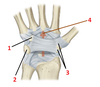

1? 3?

1: Labrum

3: Glenoid cavity

2?

Glenohumeral capsule